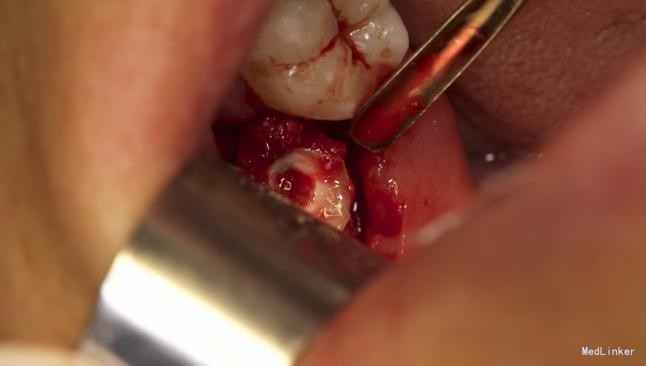

拔除术

挺好的病例,图片也很清晰,牙齿分的很好,我之前拔过类似的牙,牙齿分开后近中撬不动,最后又T型分开近中后才弄出来